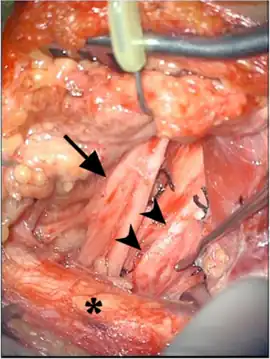

| Intraneural perineurioma image - enlarged and fibrotic lower trunk of brachial plexus arrowheads and normal divisions of upper trunk arrow ( clavicle asterisk) | |